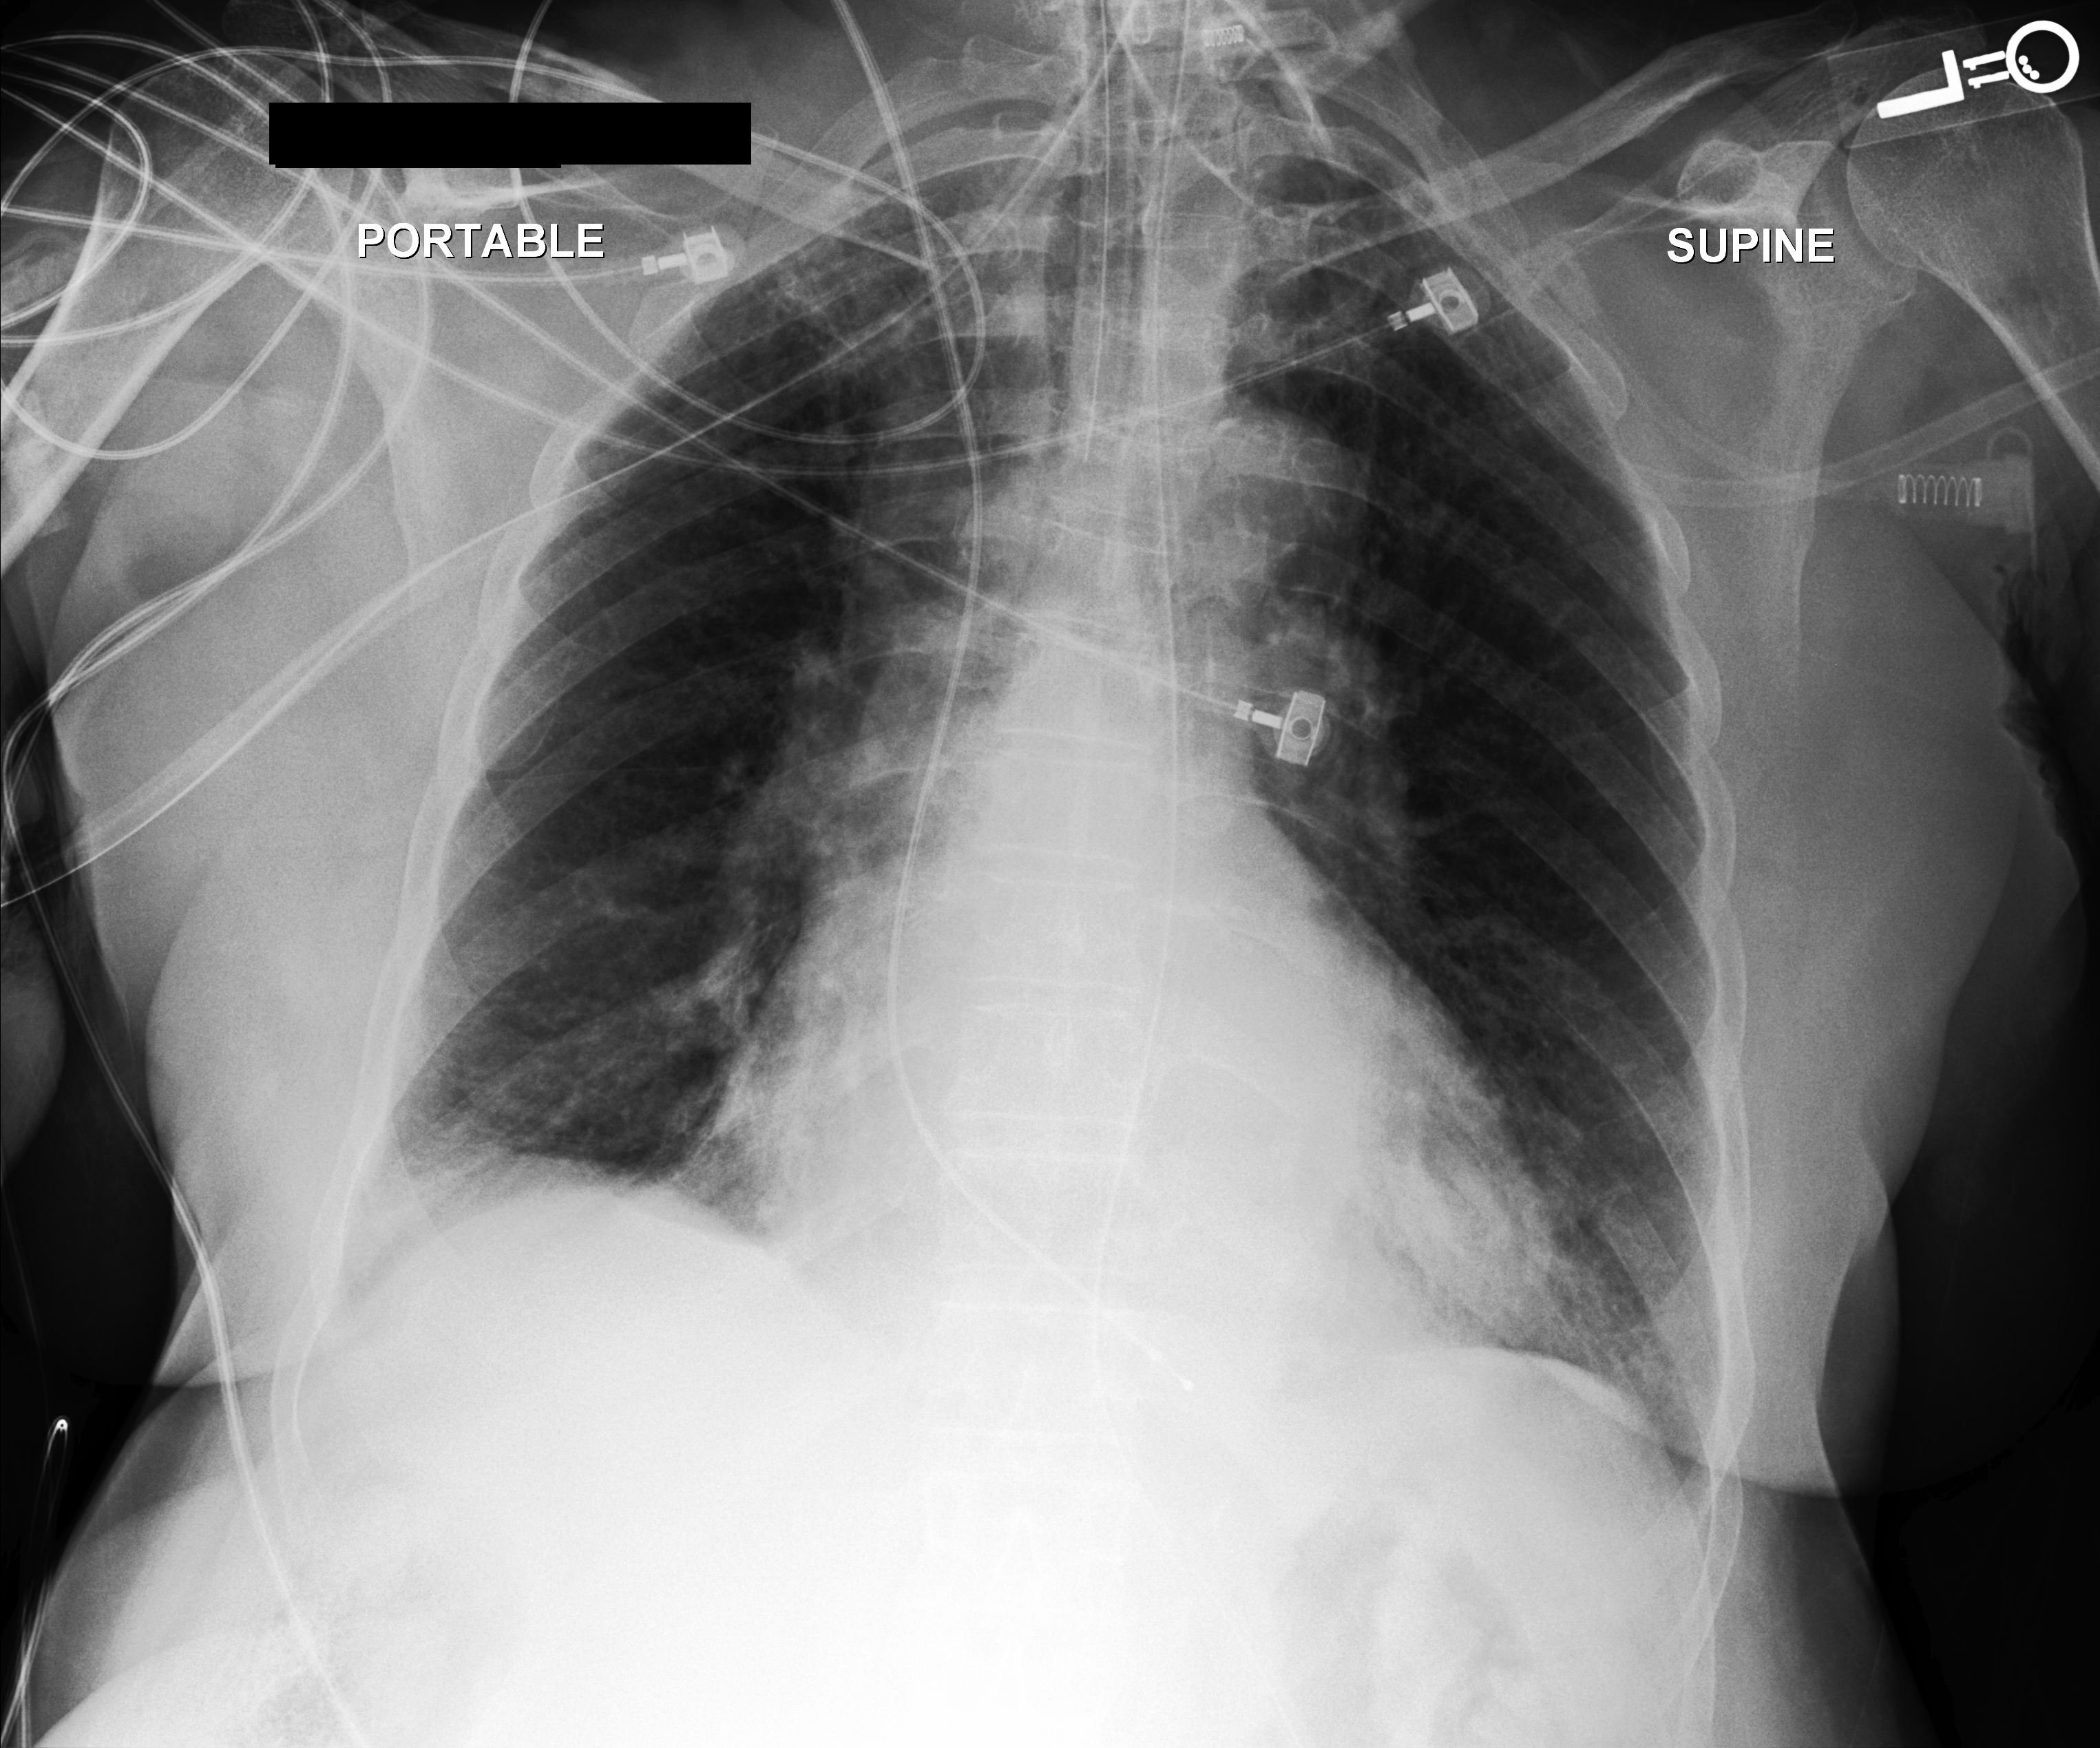

Chest X-Ray Ground Truth Our predictions

[Uncaptioned image] There is decrease in now small right pleural effusion. There is no pneumothorax. There is a new right pacer pigtail catheter. Cardiomediastinal contours are unchanged. Lines and tubes are in standard position. Left lower lobe opacities, a combination of pleural effusion and atelectasis, are unchanged. uncertain pneumonia. pleural effusion present. lung opacity present. atelectasis present. bilateral pleural effusions, left greater than right. bibasilar opacities potentially atelectasis in setting of low lung volumes. infection be excluded. frontal and lateral views of chest demonstrate low lung volumes, which accentuate bronchovascular markings. there are small bilateral pleural effusions, right greater than left, with adjacent atelectasis. there is no focal consolidation pneumothorax. cardiomediastinal silhouette is within normal limits. surgical clips are seen in right upper quadrant of abdomen. aortic arch calcifications are noted.